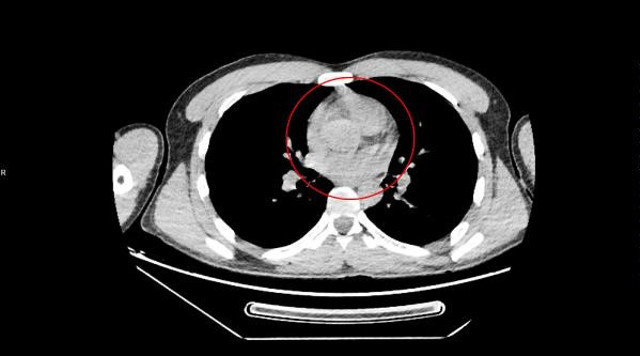

Abone olVan'dan otobüs ile Ankara'ya gelen İran uyruklu Zadeh Ahmed Narziveh, Ankara Şehirlerarası Terminal İşletmesi'nde fenalaştı. Zarziveh, çevredekilerin haber vermesiyle gelen 112 Acil Servis ekiplerinin ilk müdahalesinin ardından Ankara Şehir Hastanesi'ne kaldırıldı. Tedavi altına alınan Narziveh'in çekilen röntgen filminde midesinde cisim tespit edildi.

Ameliyata alınan Zarziveh'in midesinden 2'si patlamış 72 adet kapsül halinde uyuşturucu madde çıkarıldı. Gördükleri manzara halinde şaşkına dönen doktorlar durumu polise bildirdi. Gelen polis ekiplerinin yaptığı incelemede 890 gram uyuşturucu maddenin metamfetamin olduğu belirlendi.